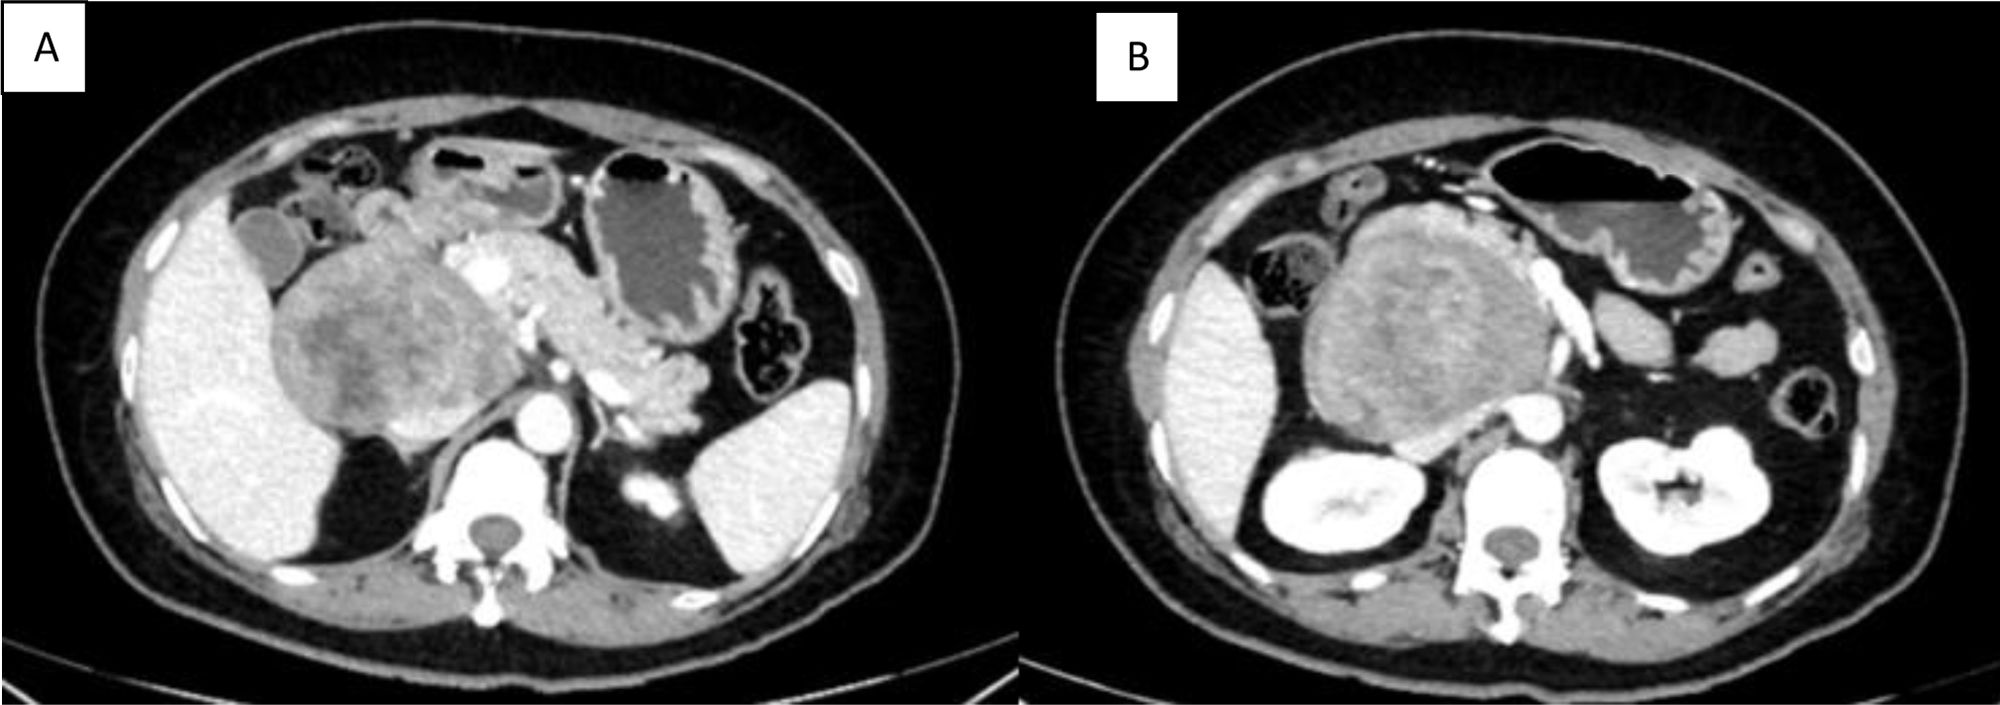

A 47-year-old woman, who had an unremarkable past medical and surgical history, sought medical attention for symptoms of abdominal pain located in the right hypochondrium and radiating to the back, with no other associated symptoms. Abdominal computed tomography (CT) scanning was ordered that revealed a heterogeneous, retroperitoneal lesion, measuring 81 × 75 × 66 mm, contiguous to the second part of the duodenum, with displacement of the head of the pancreas and partial compression of the inferior vena cava (Fig. 1 A and B).